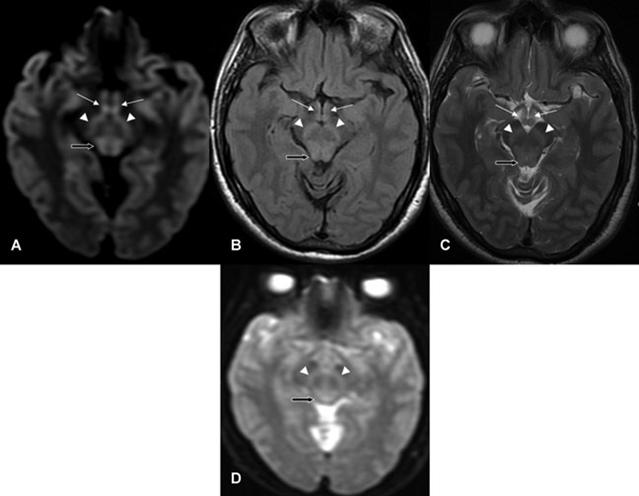

男,73歲,多發(fā)性骨髓瘤化療后惡心、嘔吐1個月。臨床表現(xiàn)為小腦性共濟失調、眼肌麻痹、雙側水平眼震。顱腦DWI示:雙側小腦半球、蚓部彌散受限(A-C)。Flair未見第3腦室周異常信號。復查DWI示:除之前病灶灶(E),還可見雙側乳頭體(F)、中腦頂蓋(G)、丘腦內側(H)彌散受限。

病例6